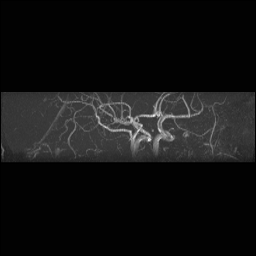

Circle of Willis, projections

For Circle of Willis projection images:

View #1